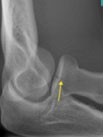

Suggest X-ray

Our Hand Therapists, Physiotherapists and Occupational Therapists are experienced in reading X-rays and CT’s for elbow dislocations and they will be able to guide your treatment depending on the severity of your dislocation.

Action Rehab Hand Therapy Clinic hand therapists can assess, advise, and treat dislocated elbows and seek specialist surgical opinion when required. Our therapists have the ability to read X-rays and CT scans and the Hand Therapist at Action Rehab Hand Therapy Clinic can assess medical imagery deciding the most appropriate treatment plan for your elbow dislocation.

Choosing the right hand Therapist starts with them being able to read your X-rays and then fabricate the right brace for you. The therapists at Action Rehab Hand Therapy Clinic are experienced in assessing and reading X-rays.